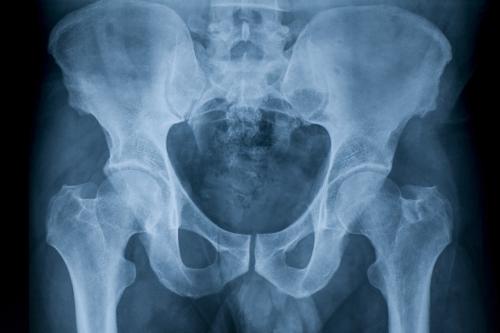

Рентген костей таза и тазобедренных суставов может проводиться в трех проекциях: переднезадней (ПЗ), заднепередней (ЗП) и латеральной (боковой). На снимке спереди видны тазовые кости от верхней части гребня подвздошной кости до проксимального отдела диафиза бедренной кости, лобковая и седалищная кости, тазобедренный сустав, запирательные отверстия, большие вертелы проксимального отдела бедра в профиль.

На снимке сбоку визуализируется крестец, копчик, пояснично-крестцовый переход, наложенные друг на друга бедренные кости и верхняя часть бедра.

Визуализируя гребень подвздошной кости, крестец, подвздошно-крестцовые сочленения, большое тазовое кольцо, лобковую и седалищную кости, проксимальный отдел бедра, рентген таза может показать: анатомические нарушение формы таза или тазобедренного сустава; переломы таза; перелом, вывих или артрит тазобедренного сустава; опухоли костей таза (остеосаркомы).

Тазобедренный сустав – это один из наиболее сложно устроенных и самых крупных суставов в организме. Основным его элементом является головка бедренной кости, размещающаяся во впадине подвздошной кости, соответствующей ей по форме. Поверхности костей сустава покрыты хрящевой тканью. Сустав снаружи ограничен суставной капсулой, окруженной мышцами, сухожилиями, нервными окончаниями и кровеносными сосудами.

Нормальное функционирование тазобедренного сустава обеспечивается хорошо развитыми ягодичными и бедренными мышцами, которые играют роль амортизаторов, принимая на себя большую часть нагрузки. Сложное строение и высокие нагрузки объясняют тот факт, что патологии этой области опорно-двигательного аппарата часто встречаются в любом возрасте.

Для точной диагностики болезней тазобедренного сустава назначается рентгенография. Основным преимуществом этого исследования является его простота, доступность и невысокая стоимость. Недостаток – вредное воздействие радиации и нечеткая визуализация мягких тканей.